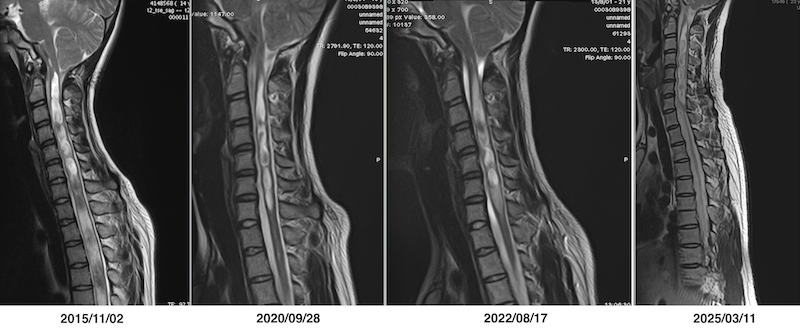

終糸切断手術後の頸髄および胸髄の脊髄空洞症の経過を示したMRI画像